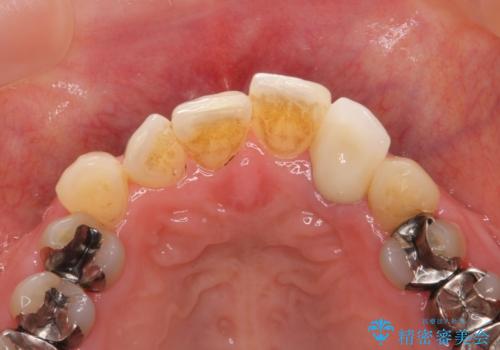

維持を保つためのファイバーコア築盛を行い、精密なジルコニアクラウン製作を行います。

自然な色調のクラウンが製作され、審美障害が改善し喜んでいただくことができました。